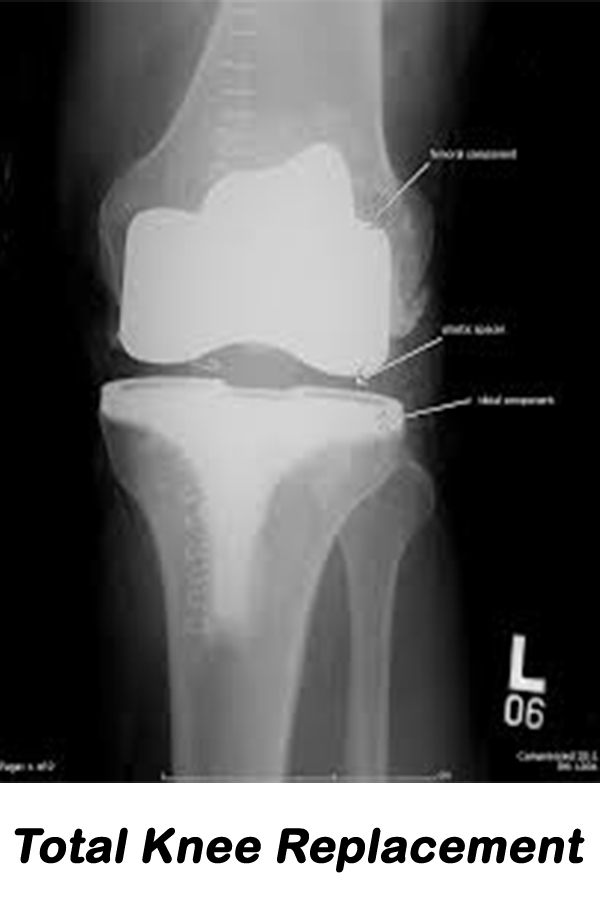

Shreerang Hospital is orthopaedic specialty hospital and is designed specifically for the orthopedic patient. Such a specialized facility and team of experts means we have the utmost in experience and understanding of the needs of orthopaedic patients meaning better outcomes, increased patient satisfaction and a reduced risk of infection or complications. Our goal is to provide you with the ultimate patient experience and excellent outcomes when undergoing orthopaedic surgery. Your care, comfort & peace of mind is constantly our top priority from pre-admission through your surgery & stay at our hospital.

Be the best place for orthopaedic & surgical, Provide quality and accessible orthopaedic & surgical services with the latest technology & equipments.

Our objective to maintain high standards of orthopaedic & surgical treatment, care and surgery. The main objective of the hospital is to offer high quality and more prominent patient care.